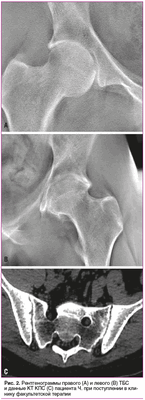

При поступлении в клинику факультетской терапии Военно-медицинской академии имени С.М. Кирова в ноябре 2020 г. дополнительно выполнена рентгенография ТБС (рис. 2, А, В).

Выявлено значительное сужение суставной щели, уплощение крыши вертлужной впадины, наличие глубоких эрозий в кортикальной пластинке по суставным поверхностям головки бедренной кости и вертлужной впадины.

Также пациенту выполнена КТ КПС (рис. 2, С). На представленных томограммах визуализируется чередование участков расширения и сужения рентгеновской суставной щели, а также множественные эрозии подвздошной кости с обеих сторон.